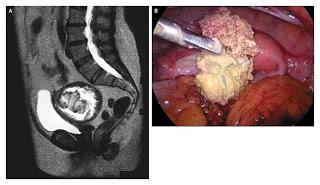

No son infrecuentes casos de una gasa que se queda por olvido o error de conteo dentro de la cavidad peritoneal tras una intervención quirúrgica como una cesárea. Esa gasa causó una peritonitis generalizada purulenta (inflamación aguda del peritoneo -membrana serosa que recubre cavidad abdominal y vísceras ahí contenidas- con presencia de pus).